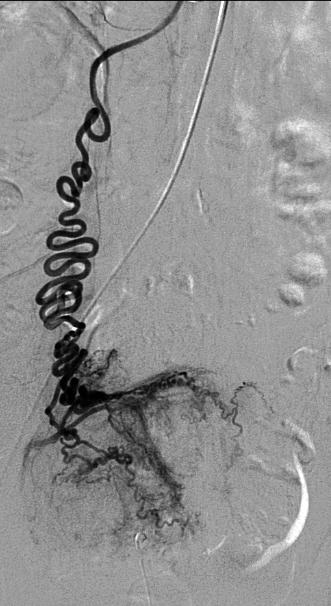

MRA 发现卵巢动脉(Kroencke et al., Radiology 2006)